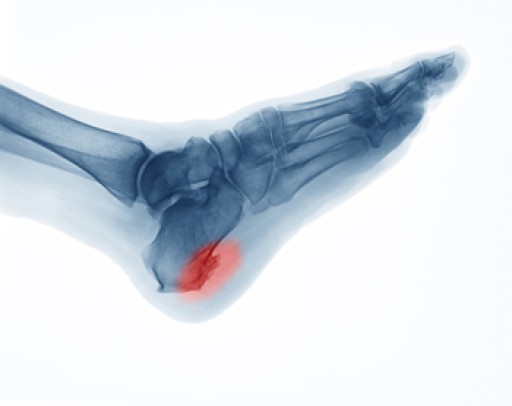

Kenali apa itu Heel Spur dan cara cara merawatnya discount, Dr Zubaidi Hj Ahmad SAKIT TUMIT HEEL SPUR Heel Spur atau calcaneal spur ialah keadaan yang disebabkan oleh pemendakan kalsium tidak normal sehingga mengakibatkan berlakunya benjolan tulang di bahagian... discount, Armels Academy APA ITU HEEL SPUR Heel Spur adalah. Facebook discount, Heel Spur Punca Simptom dan Rawatan The Diagnosa discount, 104KB 2001 null null null null null null null 1 2003 null gdUFSGid890e3M discount, Heel spur discount, Two Places Where Heel Spurs Can Form Blog discount, Heel Spurs Treatment Podiatrist Foot Doctor Punta Gorda FL 33950 and Port Charlotte FL 33952 discount, Heel Spur Causes Management Singapore Straits Podiatry discount, Foot Pain Treatment Without Injections Or Surgery discount, Plantar Fasciitis Heel Pain Stratagies to relieve pain discount, Causes and Risks of Heel Spurs Blog discount, The Definition of a Heel Spur discount, Heel Spurs Causes Symptoms and Treatment discount, Homeopathic Treatment For Heel Spur discount, Treating Bone Spurs discount, What Is a Bruised Heel discount, Bone Spurs Foot and Ankle Clinic DRHC Dubai discount, Plantar calcaneal spurs in older people longitudinal traction or vertical compression Journal of Foot and Ankle Research Full Text discount, Calcaneal Spurs Physiopedia discount, Heel Spur Taping discount, What Is a Heel Spur discount, AR Fisioterapi Apakah itu BONE SPUR Bone. Facebook discount, Painful Heel Spur Management in Singapore Podiatry Clinic discount, Plantarfasciitis What the Heel discount, Penyelesaian Heel Spur 5 Cara Iswanah Fisioterapi Atasi Iswanah Physiotheraphy discount, Heel Spur Treatment Relief The Foot Practice Singapore discount, Heel Pain Spur Pain aka Plantar Fasciitis My Bowen Therapy discount, What is Heel Spur and how to correct it relieve your pain discount, Calcaneal Spurs Physiopedia discount, Heel Pain Causes Best Treatment Options In Malaysia discount, Tumit Spur Punca Pengurusan Singapura Straits Podiatry discount, Plantar Fasciitis Home Consultant Orthopaedic Surgeon discount, Heel Spur or Calcaneal Spur discount, Iswanah Shah Alam APA ITU HEEL SPURS Plantar fasciitis Plantar fasciitis adalah keadaan di mana tisu plantar fascia yang menghubungkan tulang tumit. Instagram discount.